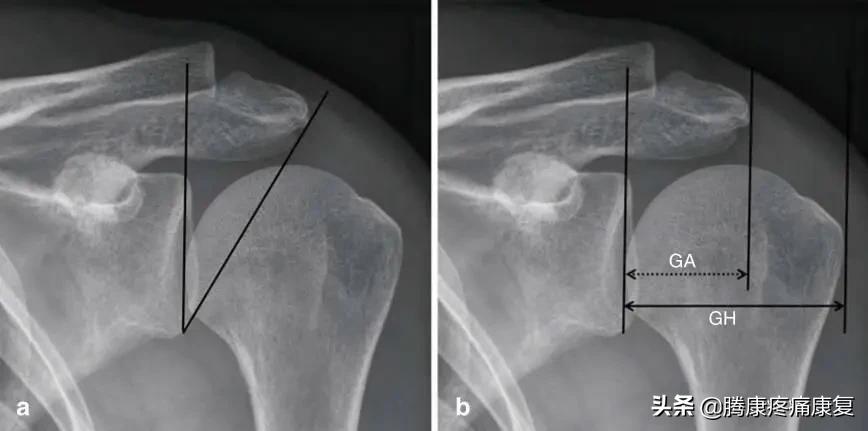

另一个危险因素是肩峰过度覆盖肩关节,可通过临界肩角(CSA)或肩肱指数(AI)进行定量评估(图4吸烟易导致肩峰下撞击综合征以及肩袖的内在损伤。

临界肩角与肩肱指数a) 临界肩角(CSA):角度(黑线)是从肩胛盂下极至肩胛盂平面和肩峰侧缘之间测量的。宽CSA是肩袖损伤的一个危险因素。b) 肩峰肱骨指数(Al):这是从肩胛盂面到肩峰外侧端的距离(GA,虚线箭头)和从肩胛骨表面到肱骨头外侧端的距离的商(GH,黑色箭头):根据定义,AI=GA/GH。高AI也是肩袖损伤的一个危险因素。